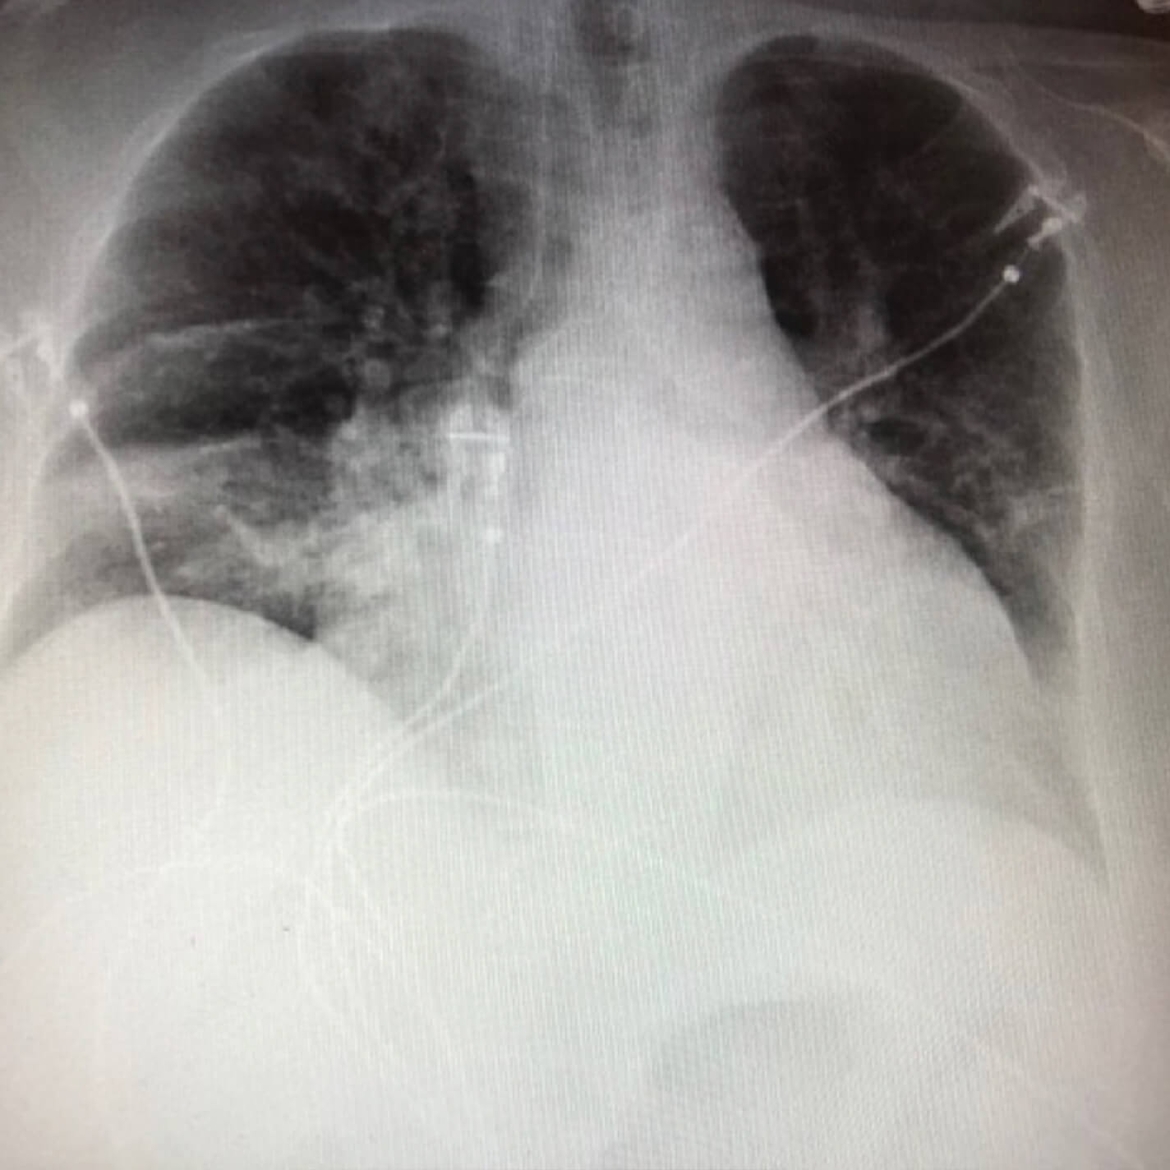

• Рентгенография грудной клетки выявила двусторонние базальные инфильтраты (слева > справа), подозрительные на пневмонию

Первичная рентгенография грудной клетки